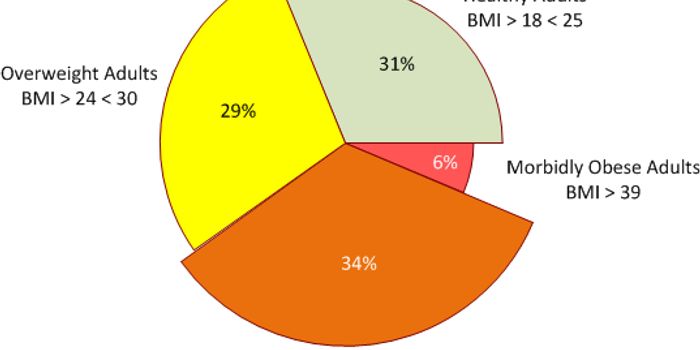

DEC 09, 2017CardiologyStudies in the past have linked obesity with better outcomes for people with heart disease although obesity has also his ...